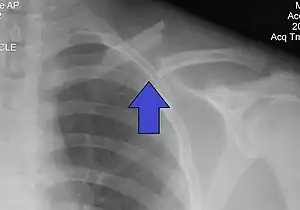

The basic method to check for a clavicle fracture is by an X-ray of the clavicle to determine the fracture type and extent of injury. In former times, X-rays were taken of both clavicle bones for comparison purposes. Due to the curved shape in a tilted plane X-rays are typically oriented with ~15° upwards facing tilt from the front. In more severe cases, a computerized tomography (CT) or magnetic resonance imaging (MRI) scan is taken. However, the standard method of diagnosis through ultrasound imaging performed in the emergency room may be equally accurate in children.[6]

Clavicle fracture